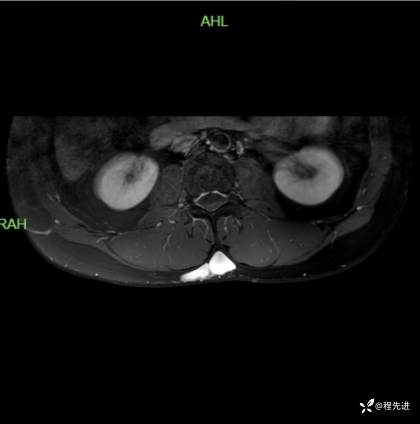

T2横断位:

T1增强压脂横断位: